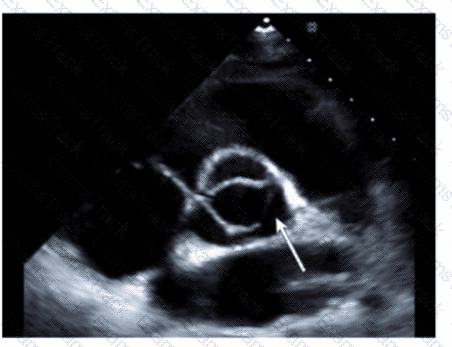

Which structure is indicated by the arrow on this image of a normal valve?